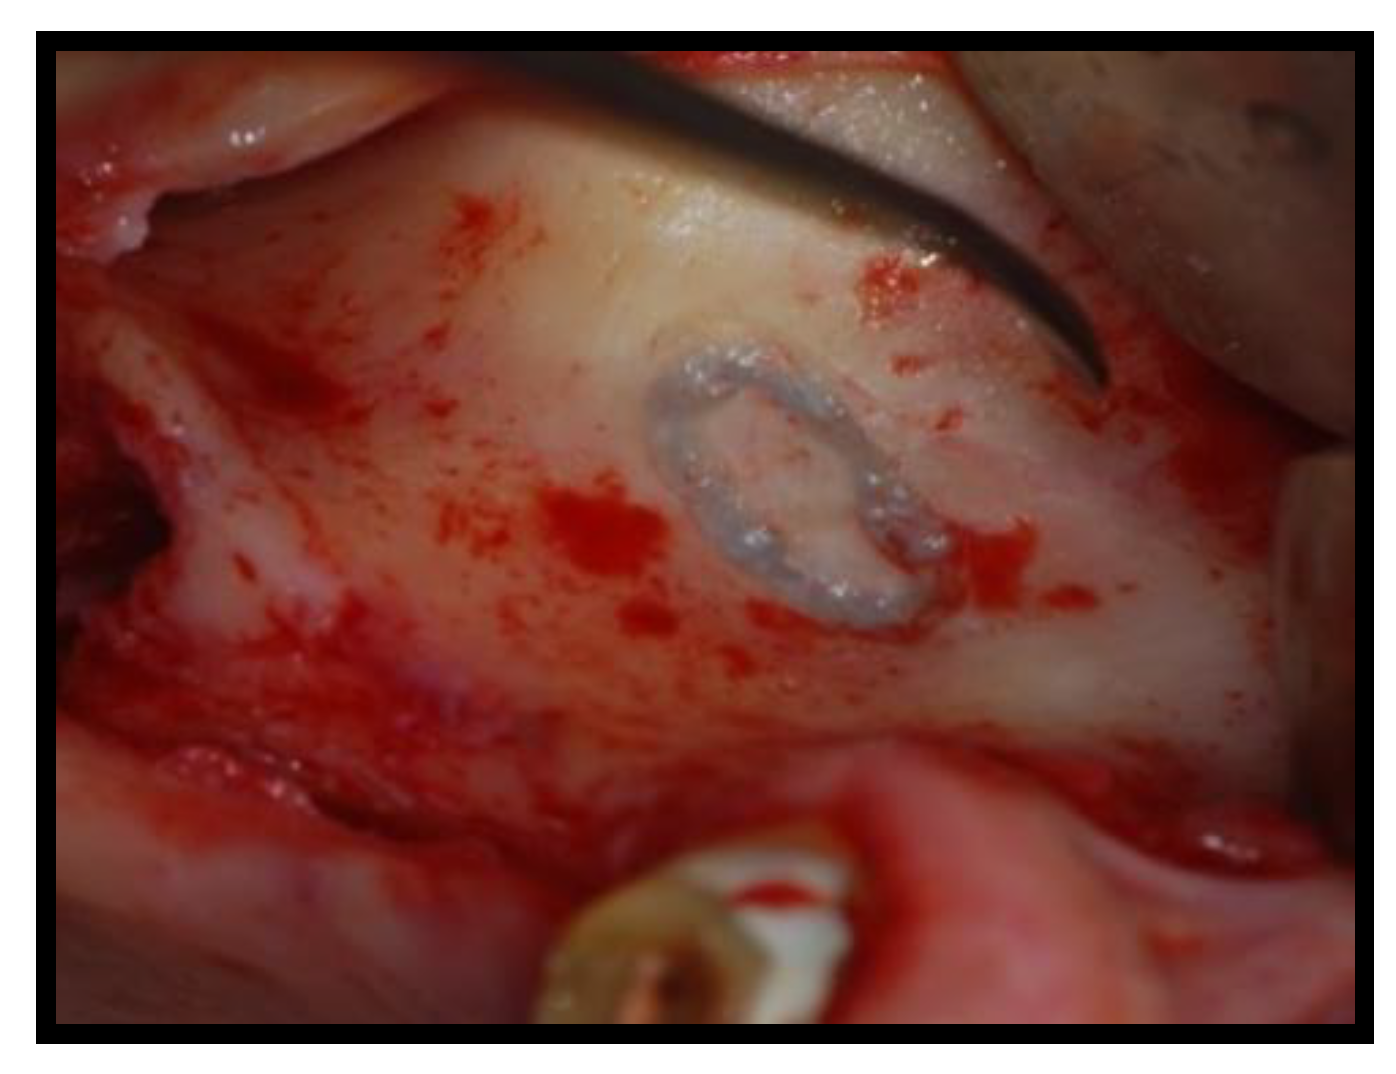

2.1. Surgical Procedures